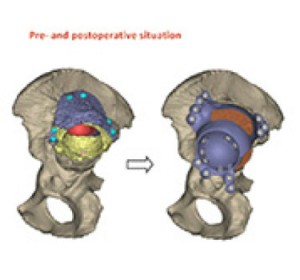

CASE 43: Using 3D Printed Guides To Achieve The Best Possible Position

.png?format=1500w) www.complexhipsurgery.com

www.complexhipsurgery.com

Patient has 3d-printed hip replacement in southampton. Case 43: using 3d printed guides to achieve the best possible position. 3d hip implant printed walk allows finally teen printing 3dprint hip1 which